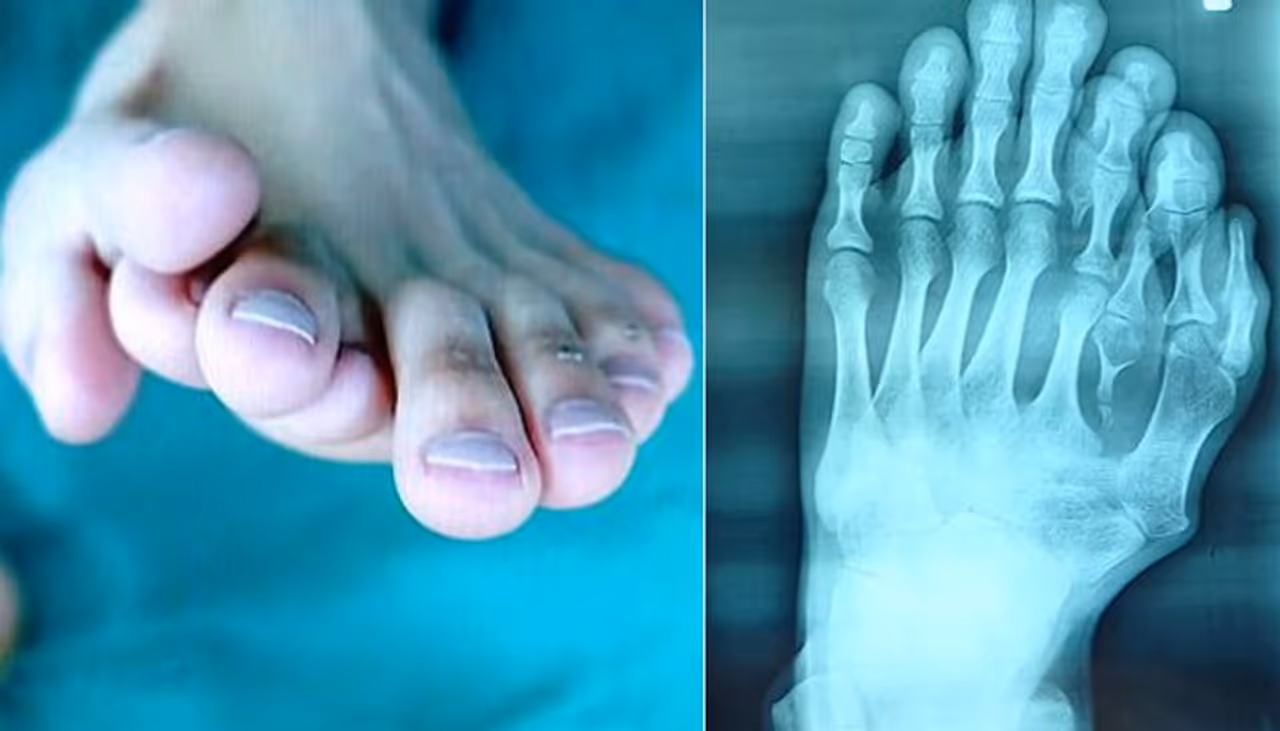

കാലില് ഒമ്പത് വിരലുകളുമായി ഒരു യുവാവ്. കേള്ക്കുമ്പോള് ഒരുപക്ഷേ ആദ്യം നിങ്ങളില് കൗതുകമായിരിക്കാം തോന്നിയിരിക്കുക.. എന്നാല് ഈ അപൂര്വ്വാവസ്ഥ കൊണ്ട് നിരവധി ബുദ്ധിമുട്ടുകളാണ് ചൈനക്കാരനായ അജുന് എന്ന യുവാവ് തന്റെ ഇരുപത്തിയൊന്ന് വര്ഷക്കാലത്തെ ജീവിതത്തിനിടയില് അനുഭവിച്ചത്.

എന്നാല് ഇരുപത് വയസ് കടന്നതോടെ അജുന് തന്റെ തീരുമാനം വീട്ടുകാര്ക്ക് മുന്നില് അവതരിപ്പിച്ചു. ഒടുവില് അവര്ക്ക് അവന് മുമ്പില് വഴങ്ങുകയല്ലാതെ മറ്റ് മാര്ഗമുണ്ടായിരുന്നില്ല. അപ്പോഴും വെല്ലുവിളികളേറെയായിരുന്നു. ഇടതുകാലില് നാല് വിരലുകളാണ് അധികമായിട്ടുള്ളത്.

ഇതില് തള്ളവിരല് പുറത്തേക്ക് തള്ളിനില്ക്കുന്ന വിരലുകളുടെ കൂട്ടത്തിലായിരുന്നു. ആദ്യം കണ്ട ഡോക്ടര്മാരെല്ലാം പറഞ്ഞത്, പുറത്തേക്ക് തള്ളിനില്ക്കുന്ന നാല് വിരലുകള് നീക്കം ചെയ്യാമെന്നാണ്. എന്നാല്, തന്റെ കാല് കാണുമ്പോള് മനോഹരമായിരിക്കണമെന്ന് അജുന് നിര്ബന്ധമുണ്ടായിരുന്നു.

അങ്ങനെ ആഗ്രഹത്തിനൊത്ത് വിജയകരമായി ശസ്ത്രക്രിയ നടത്തിത്തരാന് കഴിവുള്ള ഡോക്ടര്മാരെ തേടി, ഫോഷന് എന്ന സ്ഥലത്തെ ഒരാശുപത്രിയില്, അജുനും കുടുംബവും എത്തി. അവിടെ ഡോ. വു ക്സിയാംഗിന്റെ നേതൃത്വത്തില് ശസ്ത്രക്രിയ നടത്താമെന്നും ഒട്ടും വികലമാക്കാതെ തന്നെ കാലിനെ സാധാരണരൂപത്തിലാക്കാമെന്നും ഏറ്റു. നീണ്ട ഒമ്പത് മണിക്കൂറത്തെ ശസ്ത്രക്രിയയായിരുന്നു. അതിമനോഹരമായ തരത്തിലാണ് അധികമായ വിരലുകളെ ഡോക്ടര്മാര് നീക്കം ചെയ്തിരിക്കുന്നത്. ഇതിന്റെ ചിത്രങ്ങളും ഇപ്പോള് ആശുപത്രി അധികൃതര് പുറത്തുവിട്ടിട്ടുണ്ട്.